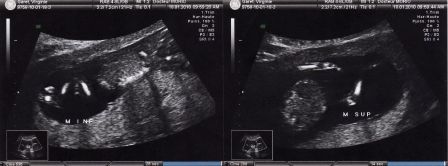

Bébé à 3 mois de grossesse

Par Virginie et Julien Garet le samedi, mai 15 2010, 20:59 - Avant la naissance - Lien permanent